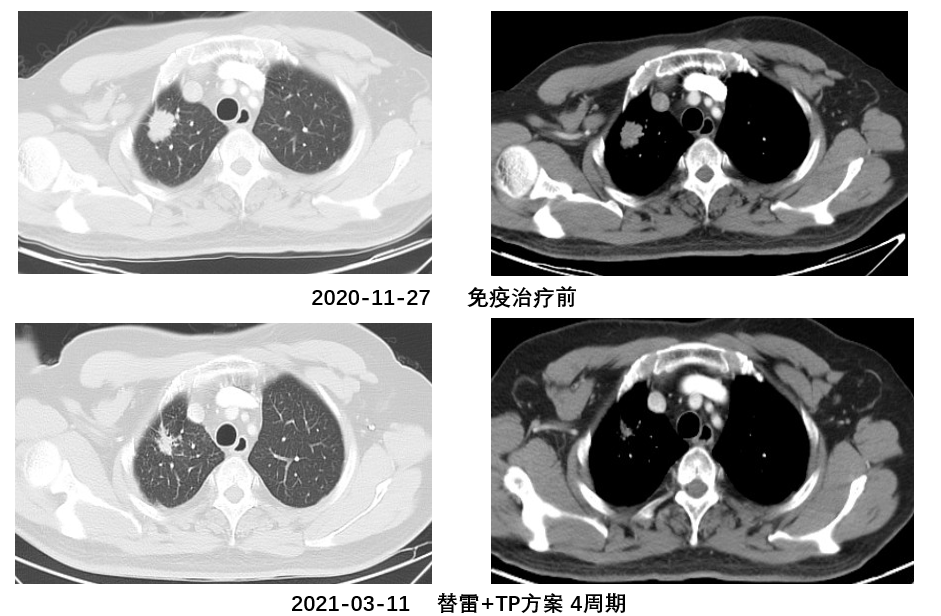

2020-12-17至2021-02-18期间:免疫+TP方案,4周期

(替雷利珠单抗200mg d1 +白蛋白紫杉醇520mg d1+卡铂830mg d1,q21d)

评估疗效:部分缓解(PR)

影像学资料